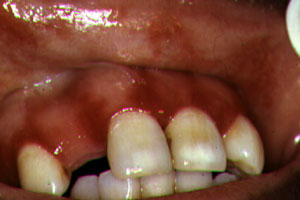

Periodontitis

ulceronecrotizante |

La

periodontitis ulceronecrotizante se manifiesta en menos

del 5% de los casos con pérdida de hueso y tejido blando en los

pacientes VIH con recuento de CD4 inferior a 200 y puede progresar a

estomatitis ulceronecrotizante Se encuentran microorganismos usuales